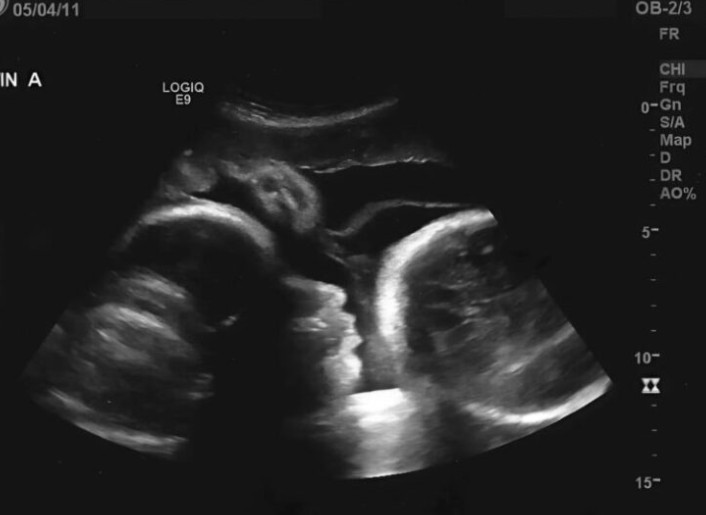

En fixant l’écran de l’échographie, le visage du praticien blêmit soudainement ; c’est d’une voix tremblante qu’il finit par lâcher la cruelle vérité. Larisa n’était pas enceinte ; les tests initiaux s’étaient révélés trompeurs. La protubérance qui déformait le ventre de la vieille femme n’était pas le fruit d’une vie naissante, mais tout au contraire, une tumeur ovarienne colossale qui consumait son organisme de l’intérieur.

Les explications du médecin furent un véritable effondrement pour Larisa. Cette sensation de « mouvement » n’était que la pression exercée par la masse tumorale sur ses organes vitaux. Pire encore, pour avoir tant tardé à solliciter une aide médicale, les cellules cancéreuses s’étaient propagées dans tout son corps. « Si vous étiez venue dès le début, nous aurions pu vous sauver, mais la situation est désormais critique », lui annonça le docteur, le visage marqué par l’impuissance.